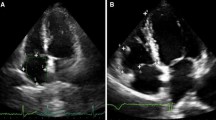

Cor pulmonale can be defined as the clinical setting in which the right side of the heart, in particular the right ventricle (RV), is affected by a pressure overload that induces changes of RV function and morphology. Depending on the duration of time in which the increased RV afterload is established, it is possible to distinguish an acute cor pulmonale from a chronic form of the disease. The most common condition responsible for the acute type is acute pulmonary embolism (APE), whereas the chronic cor pulmonale is usually caused by chronic obstructive pulmonary disease (COPD) [1], followed by idiopathic pulmonary fibrosis (IPF) and chronic thromboembolic pulmonary hypertension (CTEPH). Commonly, these diseases induce a chronic hypoxemia and/or a remodelling of the pulmonary circulation [2], which forces the RV to adapt in compensation for the increased mechanical work required to pump blood through the lungs. In this regard, the echocardiographic evaluation is a cornerstone in both the diagnosis and the prognostic stratification of these patients. In general, when RV afterload is acutely increased, the results are a dilatation and an impaired function, whereas when the pressure increase is gradual, the RV has time to adapt and is more likely to present complex remodelling features, including RV hypertrophy. Figure 1 outlines the 2D-echocardiographic views that should be always assessed in order to pursue a thorough evaluation of the RV. This review attempts to present the current evidences of the role of echocardiography in both acute and chronic cor pulmonale, including new techniques, such as 3-dimensional echocardiography (3DE) and speckle tracking echocardiography (STE), which have proven valuable tools for distinguishing between the acute and the chronic form.

Echocardiographic assessment of the right ventricle. This figure shows the main four 2D-echocardiographic views that should be assessed for a thorough evaluation of the right ventricle (RV): parasternal long axis view (PLAX), short axis view (SAX), apical 4-chamber view, and subcostal view. CH, chambers; LA, left atrium; LV, left ventricle; PLAX, parasternal long-axis view; PV, pulmonary valve; RA, right atrium; RV, right ventricle; RVIT, right ventricular inflow tract; RVOT, right ventricular outflow tract; SAX, short axis; TV, tricuspid valve